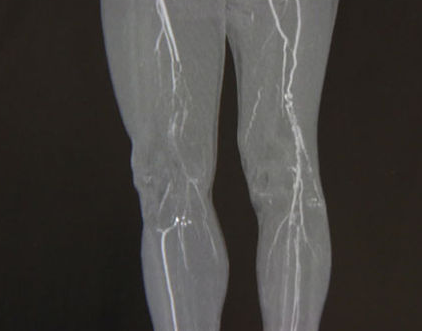

우선 종아리 근육 통증이 느껴진다면 가장 먼저 의심해 볼 필요가 있는 것이 바로 종아리 혈액순환 장애입니다. 종아리는 신체 부위 특성상 제일 하단에 위치하고 있어서 혈액순환이 잘 되지 않을 수 있습니다.

혈액순환이 잘 되지 않기 때문에 많이 걷거나 운동을 할 경우에 종아리가 붓거나 통증이 느껴질 수 있습니다. 또한 평소 종아리 근육을 사용하지 않는다면 갑자기 근육통이 올 수 있기 때문에 평소 생활습관이 중요합니다.